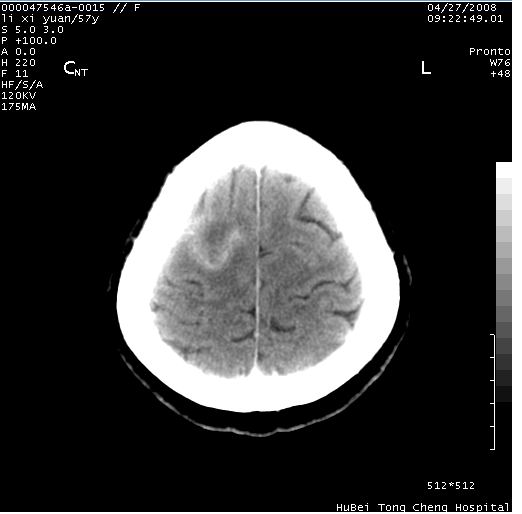

以下是引用余辉在2008-4-27 14:02:00的发言:[br]病灶位于中央沟前方?位于额叶?高密度灶,灶周水肿不明显,病灶似沿脑沟走行,强化明显,局部层面呈现环状强化,考虑1脑表面血管性疾病,如血管瘤,血管扩张,灶内血栓形成,其次考虑肿瘤如脑膜瘤、转移瘤,胶母等

以下是引用形影不离在2008-4-27 14:13:00的发言:[br]考虑胶质瘤可能性大,不排除慢性炎性肉芽肿。建议mri检查。